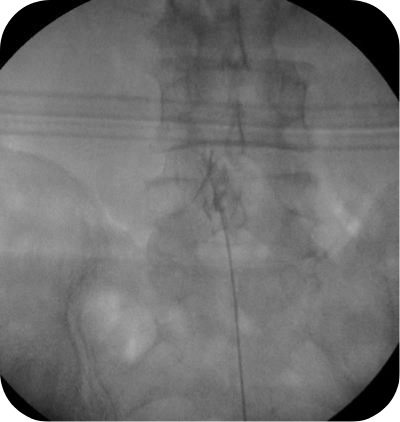

척추 꼬리뼈 부위에 국소마취를 한 후 C-Arm 을 통한 X-ray 투시장치로 병변을 직접 보면서 특수 카테터를 삽입하여 척추의 손상이 있는 부위에, 카테터를 통해 약물(고농도 식염수, 유착 방지제 등)을 주입하여 척추 신경 주위에 염증 부종을 제거합니다.